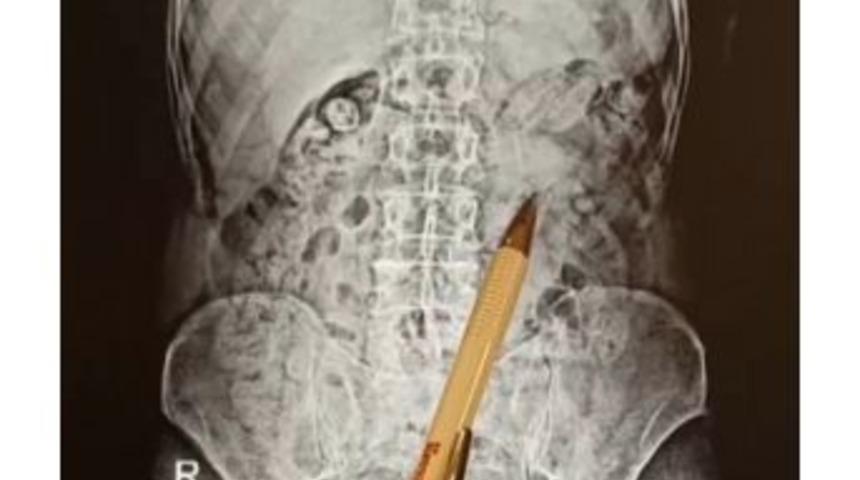

İzmir’de yaptıkları operasyonda İran uyruklu şahısların üst ve iş yeri aramalarında herhangi bir suç unsuruna rastlamayan Narkotik Şube ekipleri, şahısların uyuşturucu maddeleri mide ve bağırsaklarında sakladığını tespit etti.İzmir’de tedirgin davranışlarla etrafını gözetleyen iki şahsı fark eden Narkotik Şube ekipleri, şüpheli şahısların takibi sonucunda Torbalı ilçesinde bir iş yerinde İran uyruklu E.M. (34) ve P.S. (55) isimli şahısları yakaladı. Şahısların eşyalarında yapılan aramalarda herhangi bir suç unsuruna rastlamayan ekipler, şahısların şüpheli hareketleri üzerine yapılan çalışmalarda uyuşturucu maddeyi yutarak vücutlarına saklamış olabilecekleri değerlendirerek harekete geçti.Uygulanan tıbbi müdahale sonucunda şahısların mide ve bağırsak bölümünde yabancı cisimlerin varlığı tespit edildi. Her iki şahsın mide ve bağırsak bölümünden çıkan 116 adet, toplam ağırlığı 810 gram metamfetamin maddesi ele geçirildi.Tamamlanan işlemlerin ardından adli makamlara sevk edilen E.M., P.S. isimli şahıslar çıkarıldıkları mahkemece tutuklanarak cezaevine gönderildi.